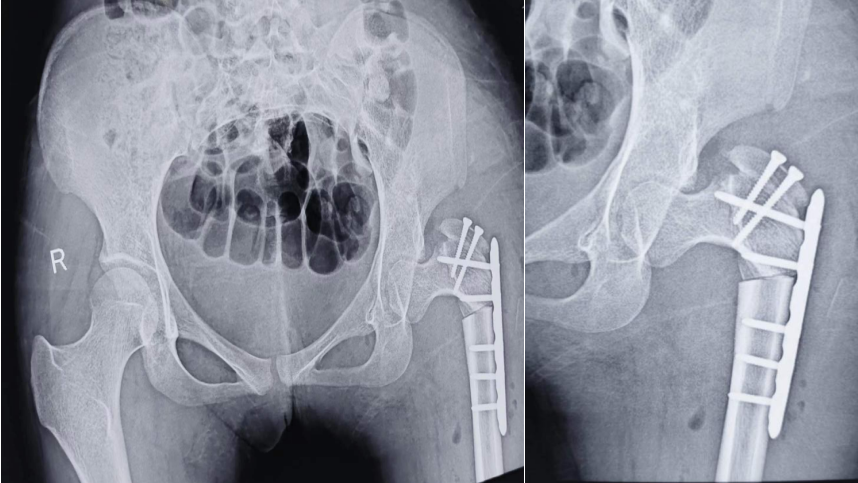

术后影像资料

患者女性,16岁,自学步以来就呈现跛行步态,近一年疼痛加剧,严重影响日常生活,遂来兰大二院就诊。入院后,骨科主任夏亚一教授结合患者病史及检查、检验结果,明确诊断为发育性髋关节发育不良(左侧完全脱位)。由于长期髋关节脱位导致双下肢不等长活动跛行,已造成继发骨盆倾斜及脊柱侧弯畸形,为保留自身关节并纠正脊柱侧弯畸形,经讨论评估后拟为患者实施改良髋关节复位髋关节囊成形术(Colonna手术)。手术由解放军总医院程徽教授和兰大二院骨科姚长江副主任医师共同完成,术中用时2.5个小时,术后出血量小,复查左股骨头已完全复位于人造髋臼内,目前临床疗效满意,可以达到推迟关节置换甚至避免置换的目的。